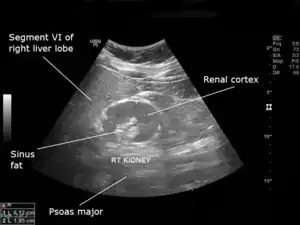

| An ultrasound scan of a hypoplastic right kidney in an adult male. | |

| Diagnostic method | Ultrasound |

Hypoplastic kidneys are prone to infection and kidney stone formation,[5] have a reduced nephron number,[4] but normal corticomedullary differentiation.[1][10]

Diagnosis is typically through ultrasonography.[1]